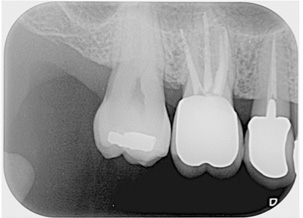

多根根管治療

治療前